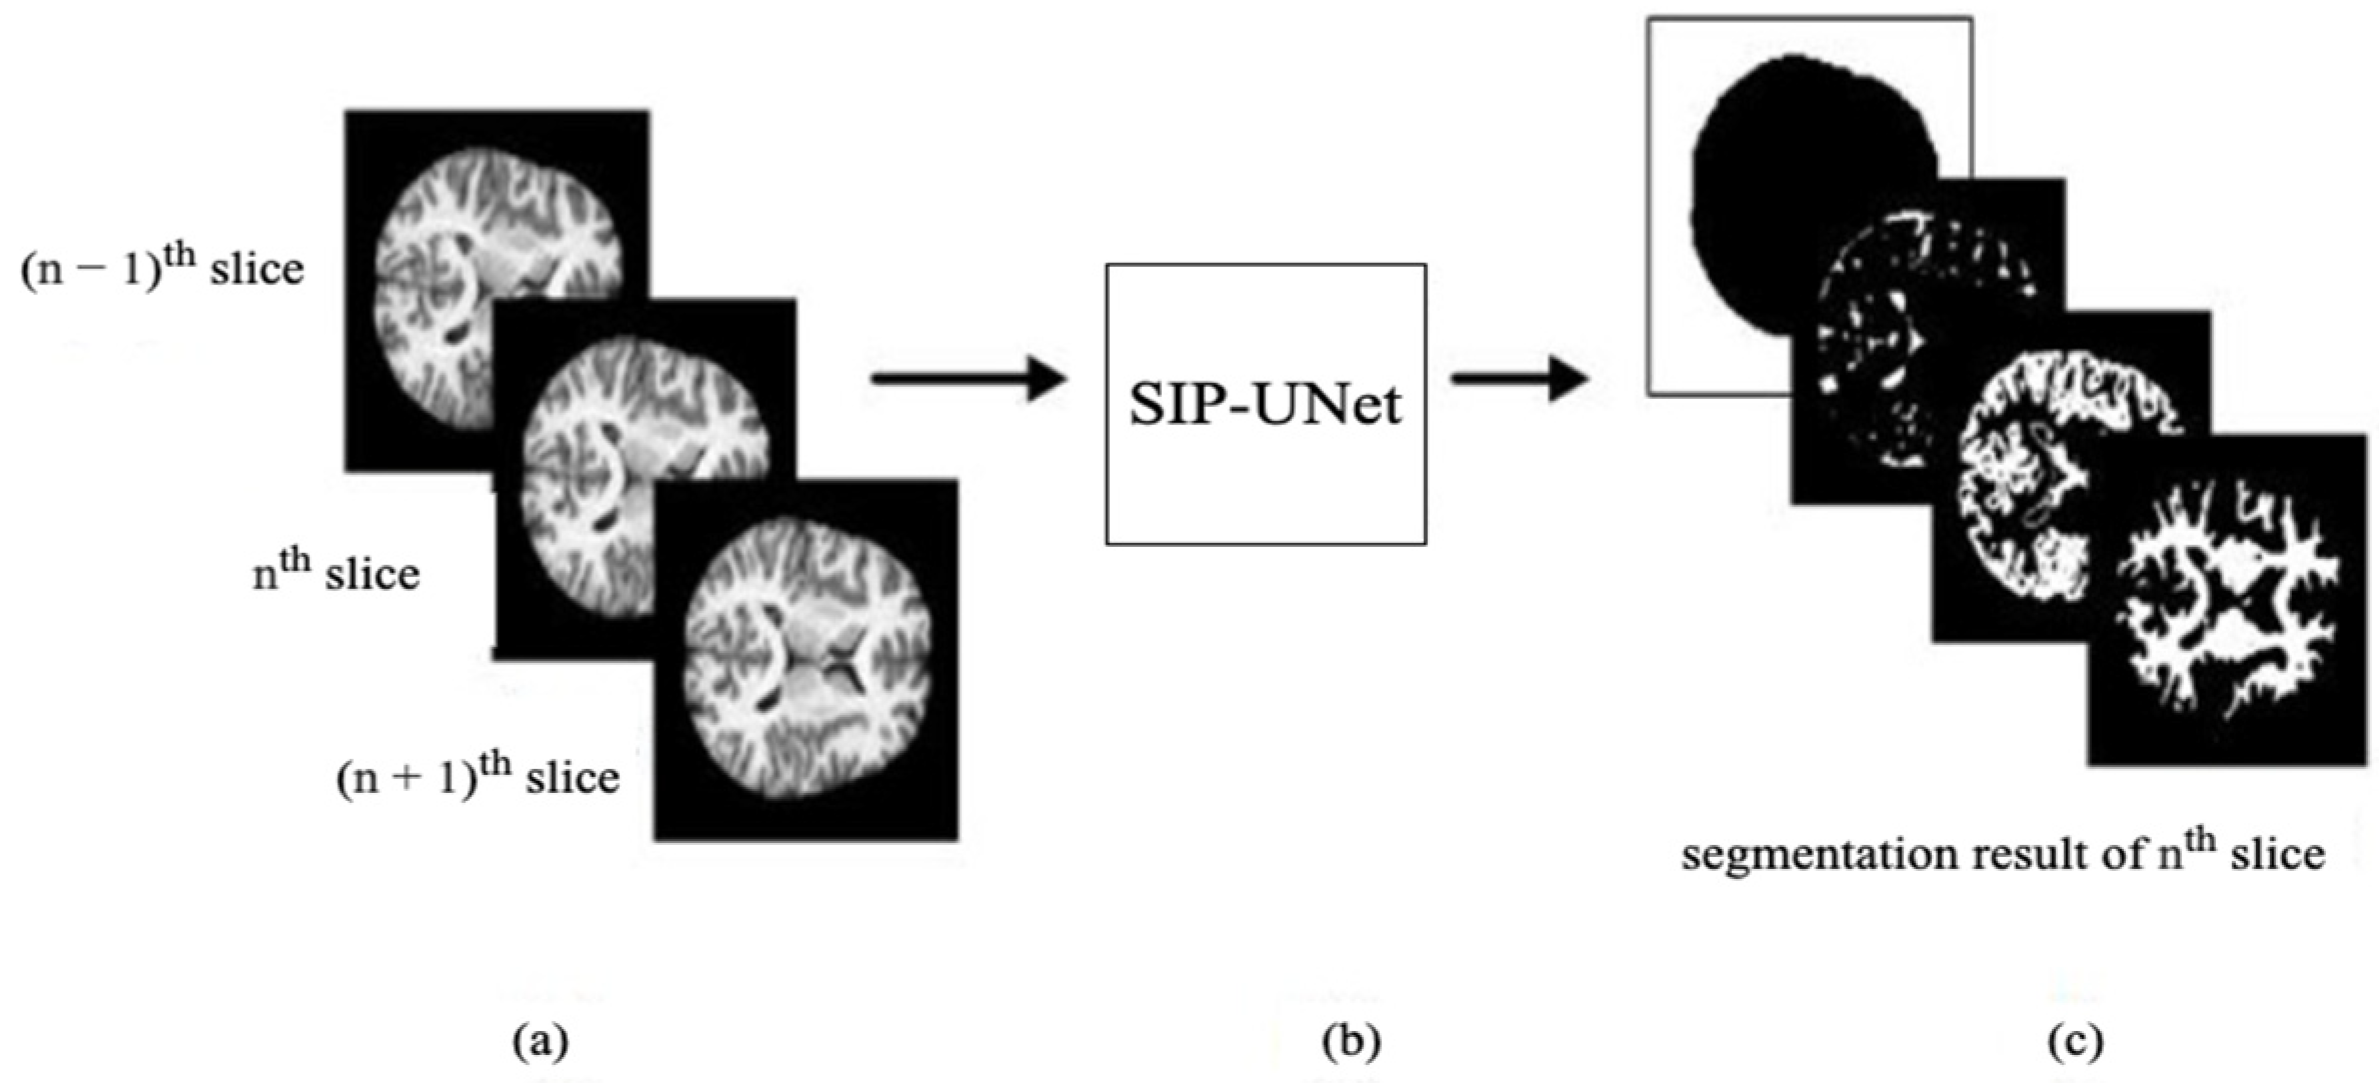

- We propose to use multiple slices as input that include neighboring slices, to extract correlated information from them.

- We introduce a novel parallel UNet to preserve individual spatial information of each input slice.

- We propose integration of the outputs of parallel Unets using a residual network with late fusion to improve the performance.

2.2. Method

2.2.1. Parallel UNet